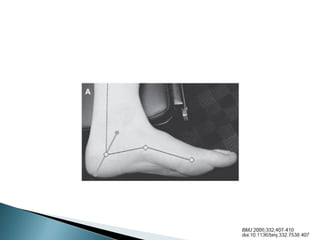

 La arteria dorsal del pie

 Rama calcáneo de la tibial posterior

 Rama calcánea de la arteria peroneal

 Arteria plantar media

 Arteria plantar lateral. Plantar interna e interna

profunda cara interna y central de la planta

 Digital común y arterias digitales cara plantar

del antepie

 Calcáneos de t. posterior y peroneal el talón